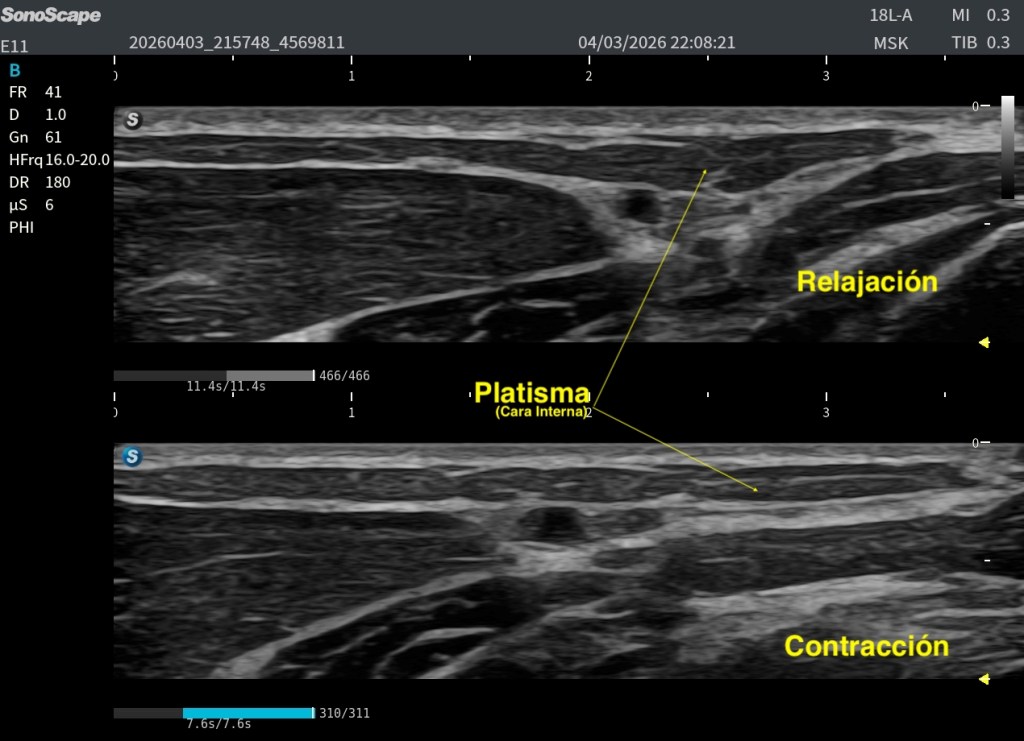

Un aspecto especialmente útil para su reconocimiento es su comportamiento dinámico. En el caso que da soporte a este post, al solicitar la contracción al paciente, se observa que las fibras laterales tienden a engrosarse, mientras que las fibras mediales se aplanan.

La alteración más habitual no es su ausencia, sino su cambio estructural con la edad. Las conocidas bandas platismales representan la manifestación clínica más frecuente. Estudios ecográficos han demostrado que estas bandas corresponden a un comportamiento dinámico real del músculo: durante la contracción, el grosor del platisma aumenta significativamente dentro de la banda (≈37,9%), mientras que en las zonas adyacentes puede incluso disminuir (≈20,3%) (Van der Lei et al., 2023). Esto refuerza la idea de que no se trata solo de un fenómeno estético, sino de una reorganización funcional del músculo y su interacción con la piel y la fascia.